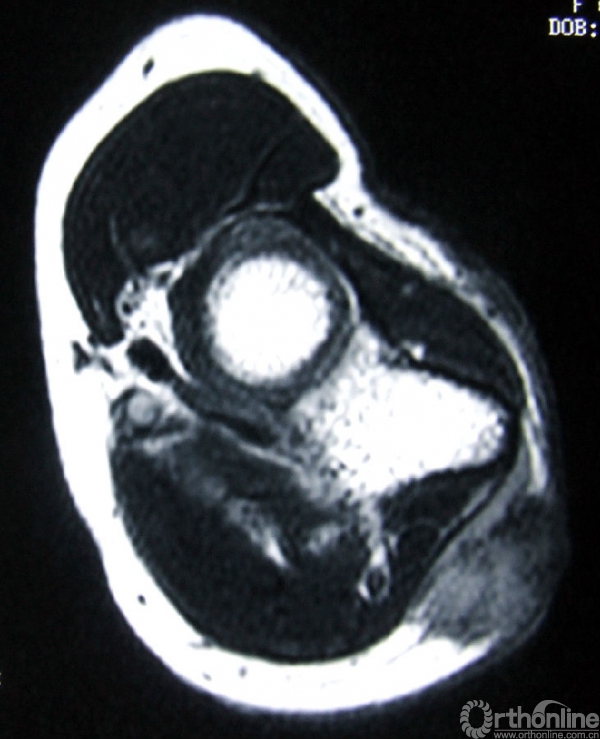

3.辅助检查:化验检查未见明显异常。B超显示右肘关节后方软组织内可见实性杂乱回声包块,1.5cm×1.0cm,界欠清,其内回声不均,可见少许血流信号。手术切口上端深处紧贴尺骨可见低回声小包块,0.9cm×0.2cm,未见血流信号。MRI(图2)示右肘关节后方皮下组织内可见软组织肿块影,边界不甚清楚,T1加权像呈现低信号,T2加权像呈中高信号,增强后T1加权像呈高信号,抑脂像亦呈现高信号。会诊病理(图3)显示成片较密集的轻度-中度间变的短梭形细胞,纤维性间质局部粘液变。初步考虑梭形细胞肉瘤Ⅱ级,可符合恶性外周神经鞘瘤形态。

图2a:T1加权像

图2b:增强后T1加权像

图2c:T2加权像

图2d:抑脂像